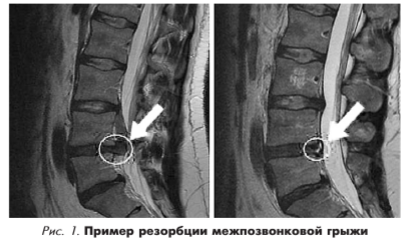

Расположение грыж в области позвоночника не отличаются в зависимости от пола и часто поражают сегменты L4—5, L5-S1, L3-L4 (поясничнокрестцовый отдел позвоночника, грыжи поясничных межпозвонковых дисков). При сравнительной характеристике размеров позвоночных грыж выявлено, что у мужчин в сегментах L5-S1, L4—5, L3—4, а у женщин в L3—4, Th12-L1, Th11 —12, L4—5 часто встречаются большие размеры грыж [7]. Пример резорбции грыж приведен на рис. 1.